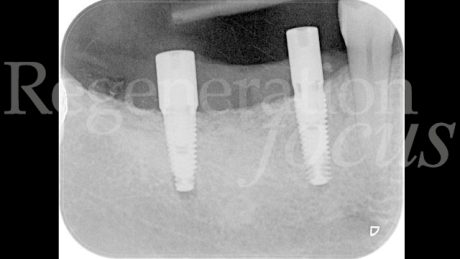

Il follow-up a 2 e 4 settimane ha documentato la guarigione per prima intenzione. A 6 mesi, la CBCT ha evidenziato eccellente integrazione dell’innesto con ottimale densità ossea (Fig. 10). La seconda fase chirurgica ha previsto la rimozione della mesh e l’inserimento simultaneo di due impianti tissue level (3.7 x 10 mm plat. 3.7 in sede 45; 3.7 x 8 mm plat. 4.5 in sede 47) caratterizzati da un design transmucoso concavo di 1.8 mm con superficie anodizzata (Matrix Line, TRI Dental Implants) (Fig. 11). Il torque di inserimento di 45 Ncm ha confermato l’ottima qualità ossea.